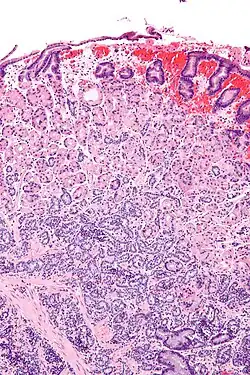

Micrograph of a neuroendocrine tumour of the stomach. H&E stain.